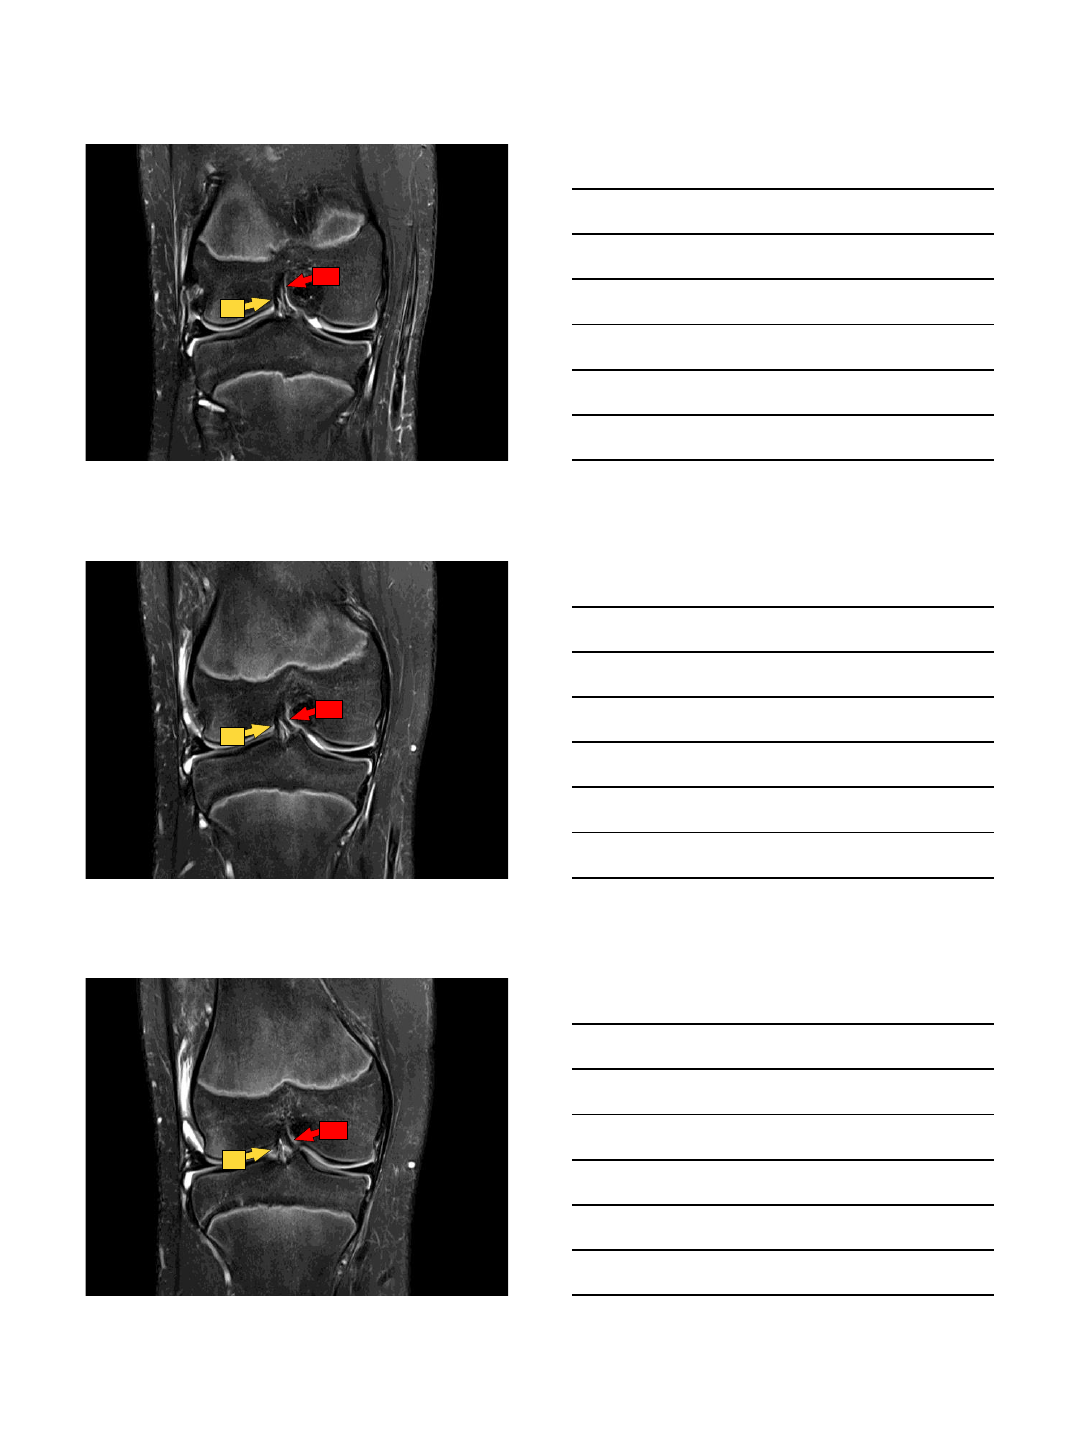

Axial:

Best for proximal to mid-portion of ligament

PL AM

10/13/2015